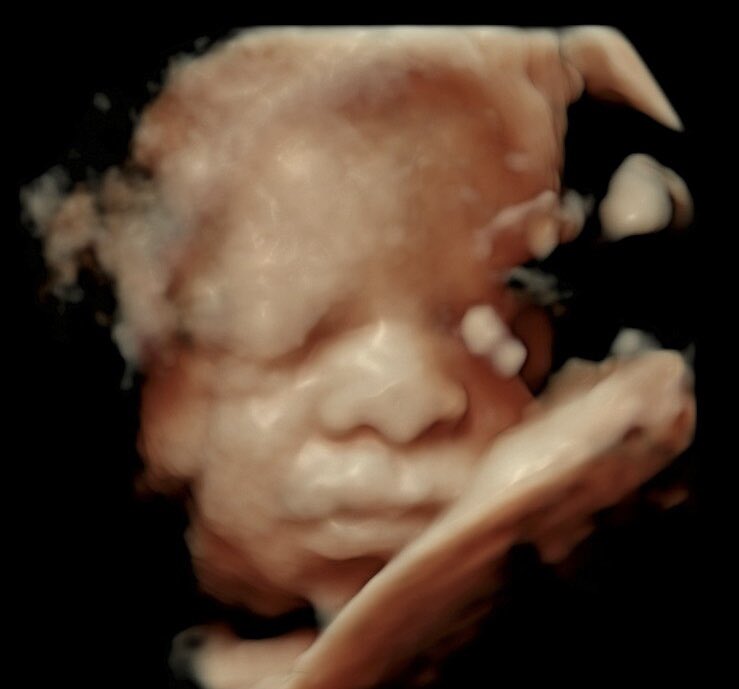

Today’s birthday was extra heart warming and special. Now at 32 weeks, we get this really special ultrasound edition of little Jay’s face. He was…. squished against the placenta but honestly I think it makes him look more like art 🩵